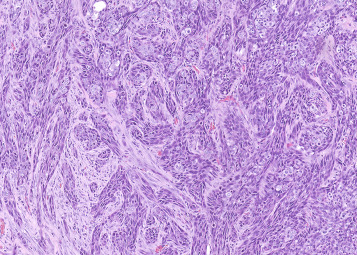

Alveolar/bronchiolar carcinomas are often poorly circumscribed (Figure 23.30, Figure 23.31 ). However, rapidly growing neoplasms may cause compression of the surrounding parenchyma and appear moderately well demarcated (Figure 23.32, Figure 23.33 ). The carcinomas may invade airways (Figure 23.34, Figure 23.35 ), pleura, or vessels and metastasize to regional lymph nodes, liver, kidney, heart, or other organs. Hallmarks of alveolar/bronchiolar carcinomas are their heterogeneous growth patterns and cellular pleomophism (Figure 23.36, Figure 23.37 ). Morphologic growth patterns vary from glandular, papillary, solid, to a mixture of these patterns. Well-differentiated carcinomas with a papillary pattern are difficult to distinguish from adenomas. Stratification of the neoplastic epithelium, solid areas of growth, cellular pleomorphism, and atypia or anaplastic cells associated with a scirrhous reaction and local invasion are indications of malignancy (Figure 23.34, Figure 23.35, Figure 23.36, Figure 23.37). Alveolar or glandular patterns of growth are usually observed only when there is a prominent connective tissue component or scirrhous reaction. Scirrhous reactions are not commonly seen in spontaneous alveolar/bronchiolar carcinomas, but occur in some carcinomas induced by exposure to particulate chemicals such as asbestos, silica, gallium arsenide, cobalt sulfate heptahydrate, cobalt metal, and other particulate chemicals. In some small neoplasms, the scirrhous reaction may be so pronounced that the neoplasm appears to arise within an area of fibrosis. Neoplastic cells within a carcinoma may be pleomorphic, and particularly anaplastic cells may be spindle shaped (Figure 23.38 ). Squamous differentiation is observed in some carcinomas and may be quite prominent (Figure 23.39 ). However, the diagnosis of squamous cell carcinoma is restricted to neoplasms that consist predominantly of squamous cells. Otherwise, neoplasms with squamous differentiation are classified as alveolar/bronchiolar carcinomas on the assumption that they are more anaplastic variants of alveolar/bronchiolar carcinomas. Neoplastic cells may also differentiate into a mucinous cell type; however, such differentiation is rare. Metastases from spontaneous alveolar/bronchiolar’ carcinomas are not commonly observed but may be more frequent with induced carcinomas. The metastatic lesions exhibit a papillary or glandular pattern of growth.

Figure 23.38.

Alveolar/bronchiolar carcinoma with anaplastic spindle cell component.